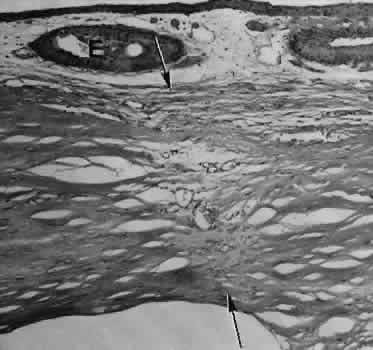

Fig. 8. Following a scleral incision, granulation tissue from episcleral tissue (E) and uveal tissue (U) will proliferate through the full extent of the sclera. The tissue will remodel along tension lines to reapproximate the tensile strength of the original tissue (Hematoxylin-eosin stain; × 28.)